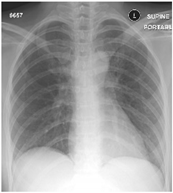

Furthermore, some of the examples of the COVID-19 positive and the healthy patients from the dataset are included in Table 5. The clinical data represent the attributes sequence, i.e., gender, age, body temperature, pulse rate, respiratory rate, blood pressure systolic, blood pressure diastolic, shortness of breath, cough, other symptoms, diabetes mellitus, hypertension, cardiac disease, dyslipoproteinemia, chronic kidney disease, and other chronic diseases.

Table 5.

Sample CXR and clinical data for the COVID-19 positive and healthy cases.